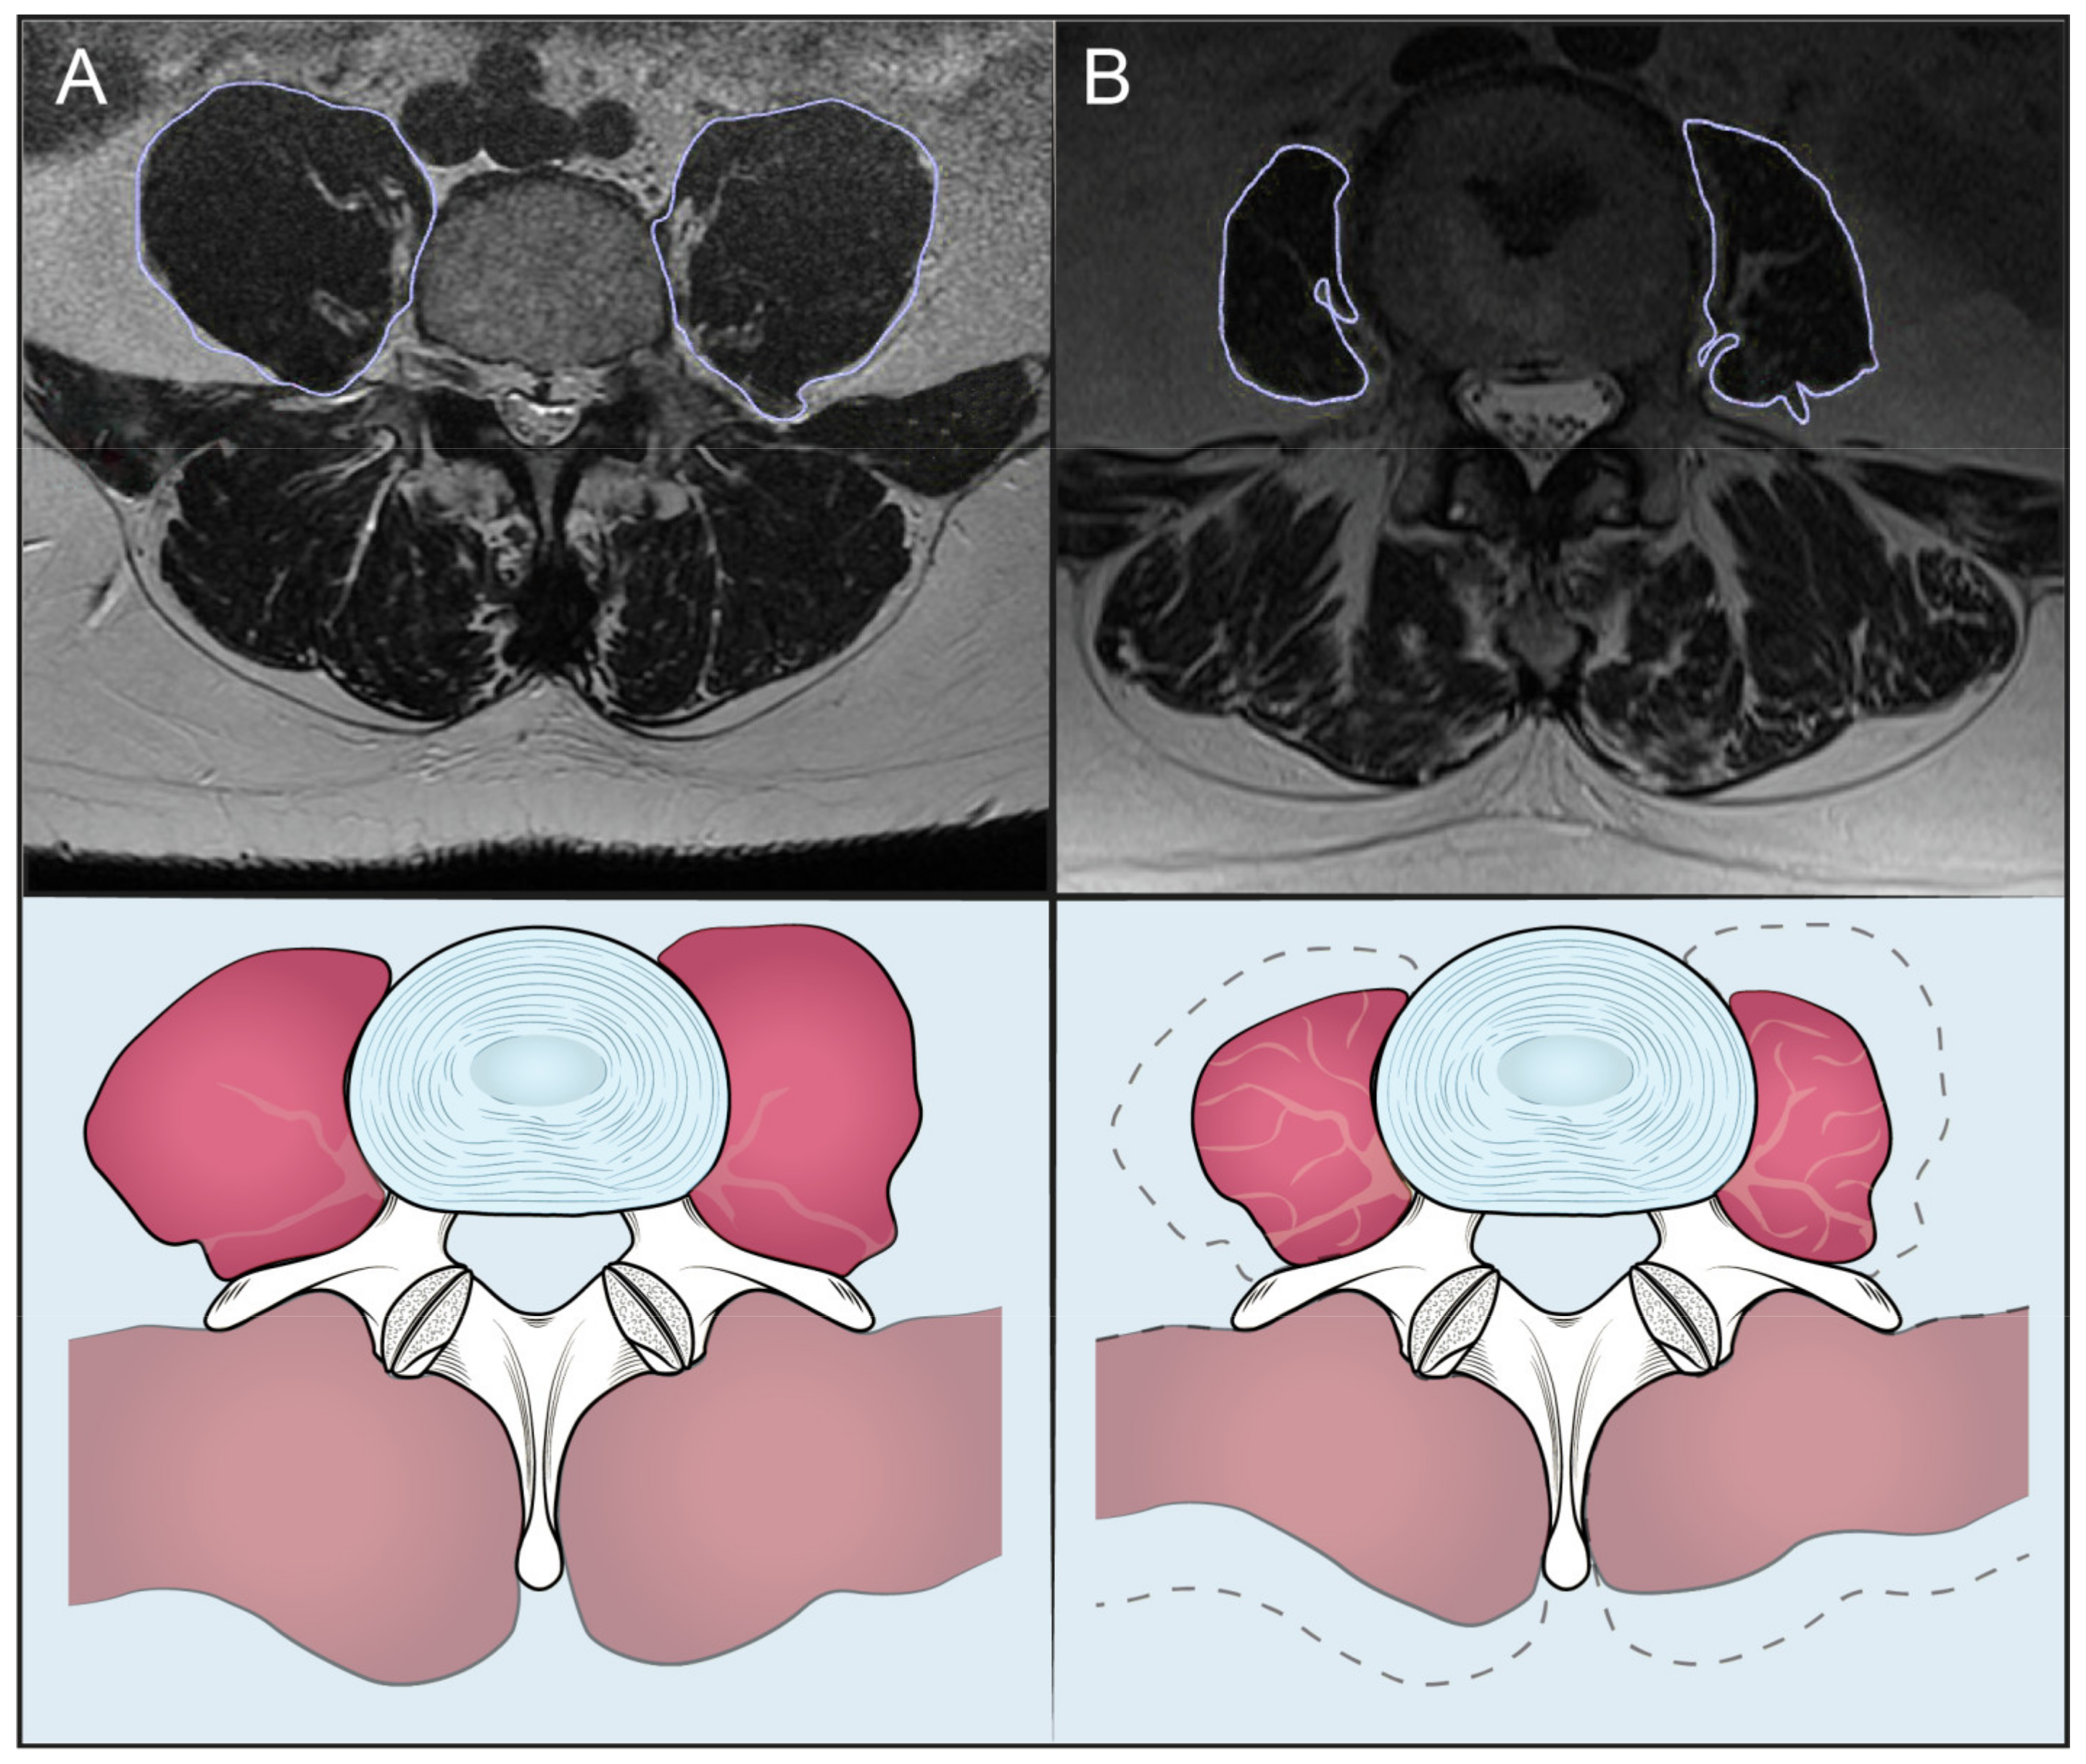

3.2. High vs. Low PLVI Patients

3.3. High vs. Low M-Score Patients